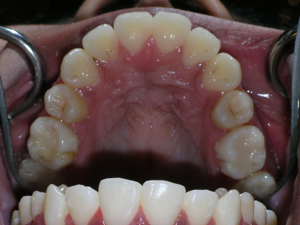

Some nice after photos.

Look at the before and after of the second molar on the right side.